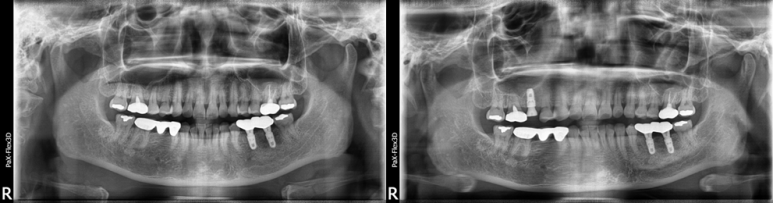

38세 남성

발치 및 임플란트 당일 식립 후 촬영한 엑스레이

(전), (후) 2022-02-05

이렇게 발치 후 즉시 식립이 가능한 환자분들 같은 경우 임플란트기간을 단축시킬 수 있는데요. 앞서 말씀드린대로 약 3개월 정도면 임플란트 치료를 모두 마칠 수 있습니다.

하지만 발치 후 적게는 3개월 혹은 그 이상 기다렸다가 임플란트를 식립해야 하는 경우도 있는데요.

치아를 발치하는 경우 원래 치아가 있던 자리가 비어있게 되고, 이 자리에 뼈가 완전하게 차올라서 임플란트를 할 수 있을 정도로 단단해질 때까지 기다려야 합니다.